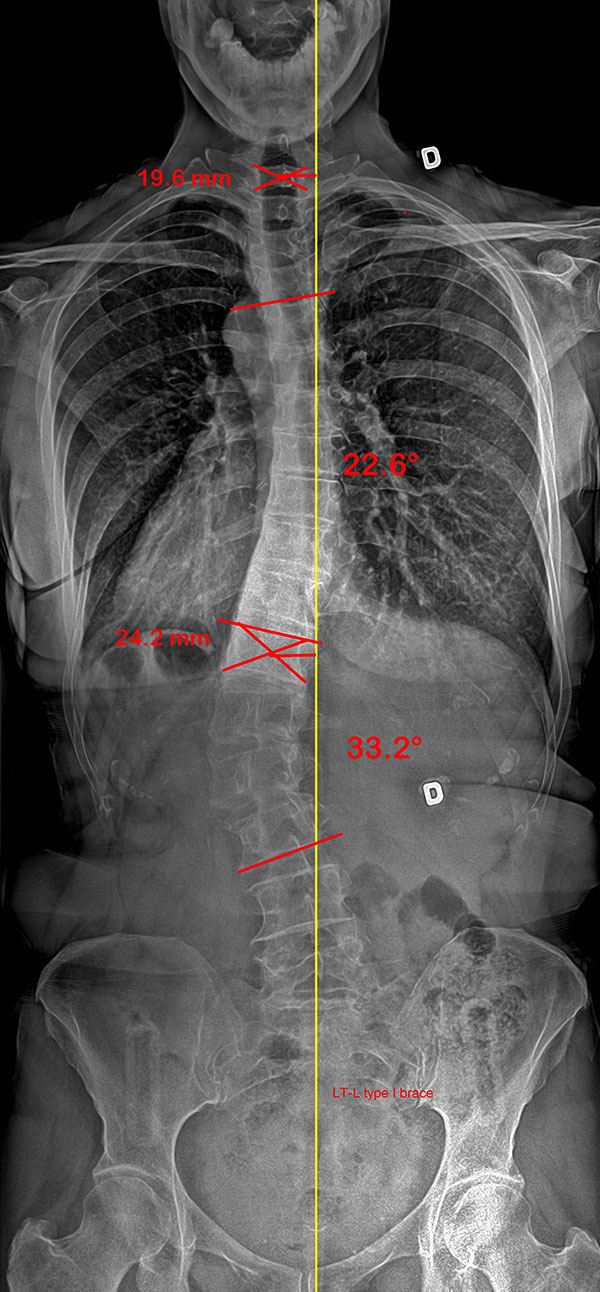

Colonne vertébrale d’une patiente scoliotique adulte, sans et avec SpineCor®

Colonne vertébrale avant SpineCor® |

Colonne vertébrale avec SpineCor® |

On remarque que, bien que la courbe n’ait pas changé de façon très significative, son alignement postural global est nettement amélioré par rapport à la ligne jaune centrale.